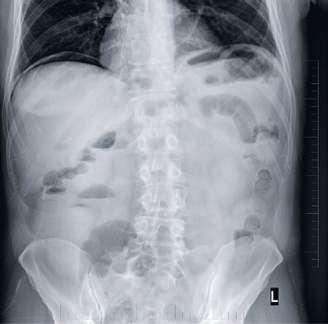

94 Akútne brucho ako príčina smrti pri náhlych úmrtiach

MUDr. Arpád Panyko, PhD., MPH